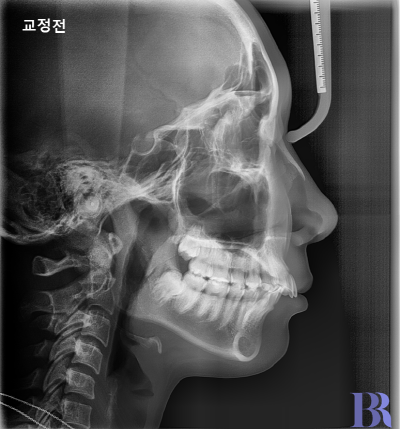

윗니가 아랫니에 비해

앞으로 많이 나와있고,

입술이 돌출된 정도는

중간 가량으로보입니다.

입이 살짝 나와보이고

치아 사이 공간도 있어요.

윗니와 아랫니 앞뒤차이가

심하게 나는 것을 볼수 있네요.